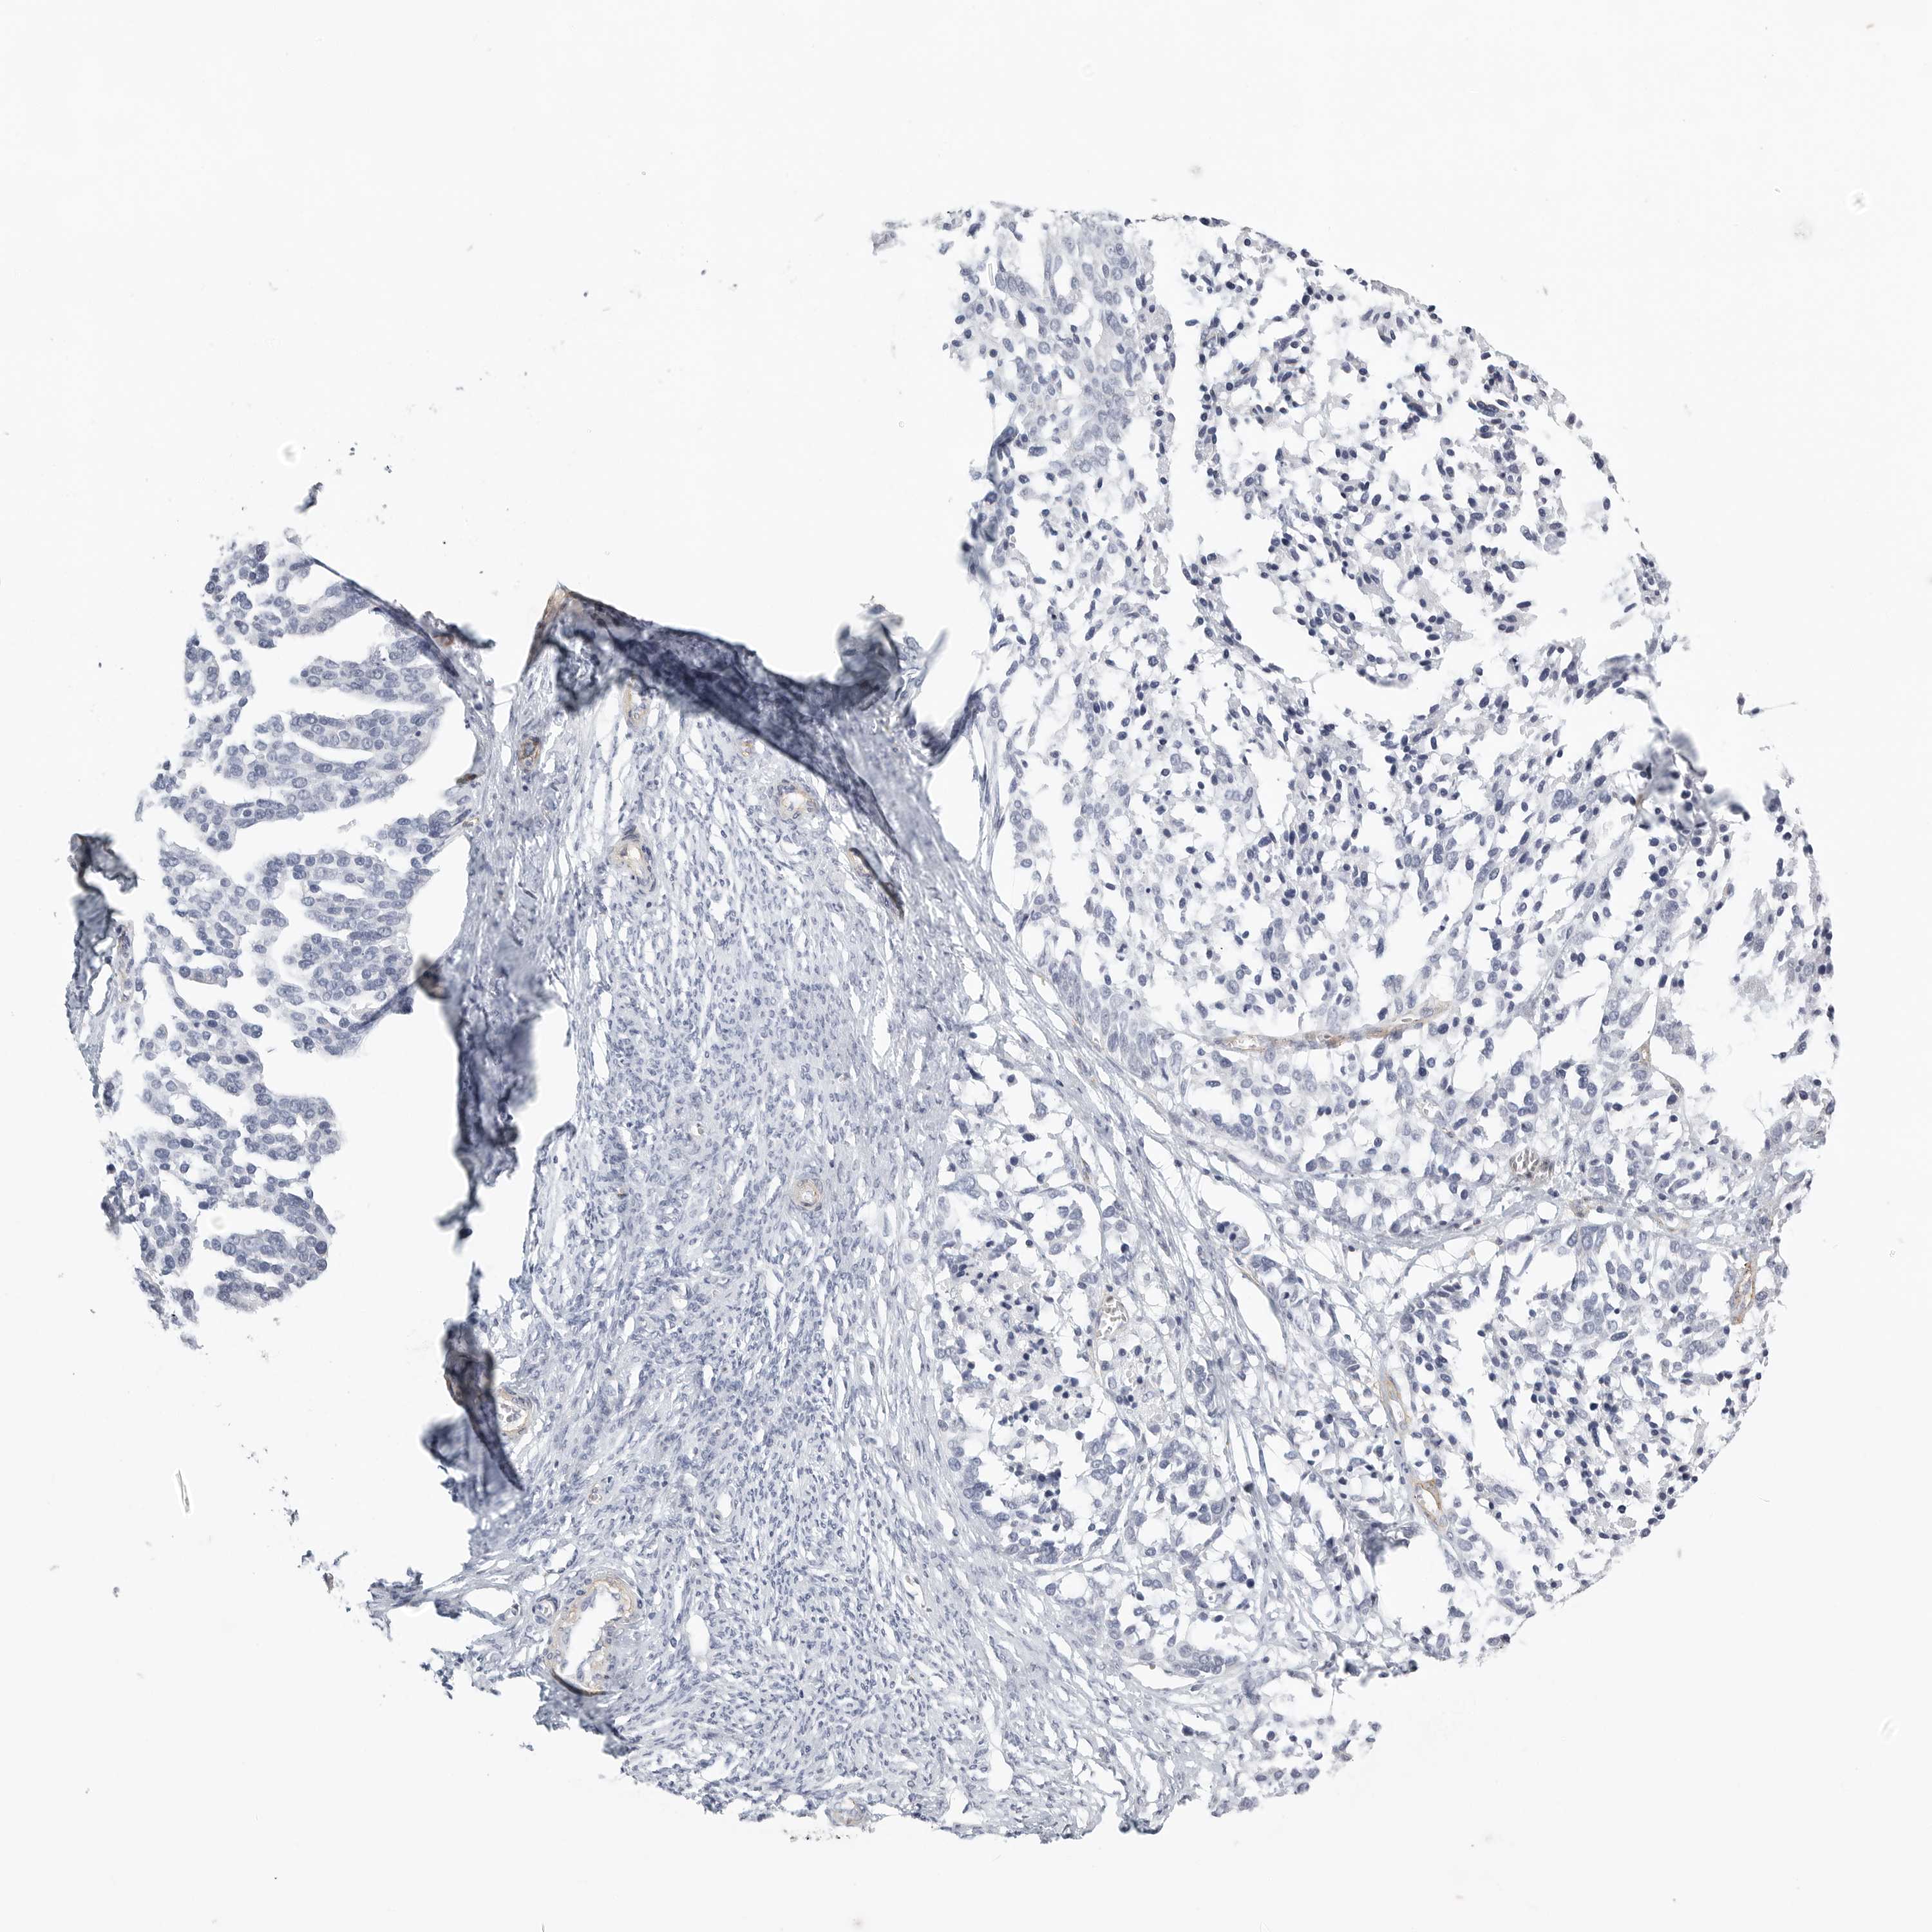

OVARIAN CANCER - Protein expressioni

A mouse-over function shows sample information and annotation data. Click on an image to view it in a full screen mode. Samples can be filtered based on level of antibody staining by selecting one or several of the following categories: high, medium, low and not detected. The assay and annotation is described here.

Note that samples used for immunohistochemistry by the Human Protein Atlas do not correspond to samples in the TCGA dataset.

Antibody stainingi

Antibody staining in the annotated cell types in the current human tissue is reported as not detected, low, medium, or high, based on conventional immunohistochemistry profiling in selected tissues. This score is based on the combination of the staining intensity and fraction of stained cells.

Each image is clickable and will lead to virtual microscopy that enables deeper exploration of all samples and also displays staining intensity scores, fraction scores and subcellular localization as well as patient and tissue information for each sample.

Antibody HPA027134

Antibody HPA027150

Antibody HPA029859

Antibody CAB022343

Staining

High

Medium

Low

Not detected

Intensity

Strong

Moderate

Weak

Negative

Quantity

>75%

75%-25%

<25%

None

Location

Nuclear

Cytoplasmic/membranous

Cytoplasmic/membranous,nuclear

Cystadenocarcinoma, serous, NOS

Carcinoma, endometroid

Cystadenocarcinoma, mucinous, NOS

Carcinoma, NOS